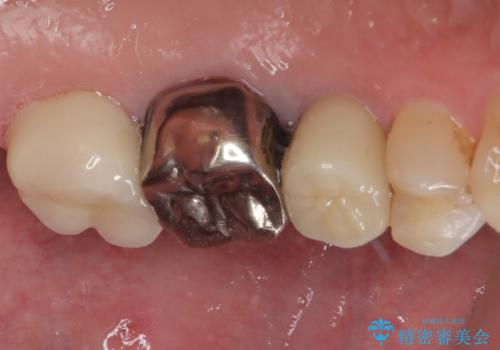

拡大鏡視野下で、セラミックの被せもの、虫歯の除去を行い、オールセラミッククラウンに適した形に整えました。

歯と歯茎の間に圧排糸と言われる糸を入れてシリコーン印象材にて型どりをしました。